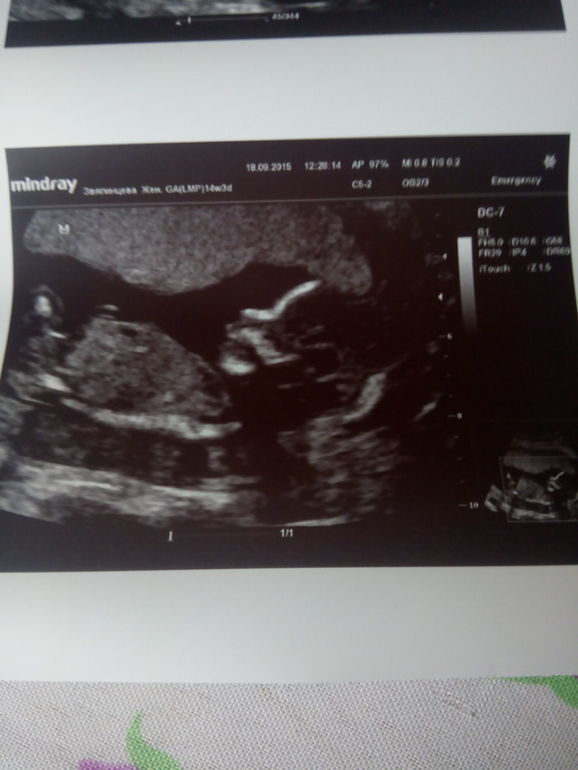

Всем большой приветик!!! Сегодня снова была на узи, пока была на дневном стационаре, простыла и отправили меня домой, сегодня позвонили и сказали чтобы в понедельник принесла узи, хотят посмотреть есть гипертонус или нет. Девочки.... нет его этого ВРЕДНОГО ТОНУСА!!! У нас всё отлично, срок на сегодня 14 недель 3 дня, а по размерам плода срок 15 недель, ЧСС 163, стручок так и не вырос, ещё раз сказала девчушка)))) ну и конечно фото)))

вот такие мы уже большие)))) и красивые)))) До встречи)))